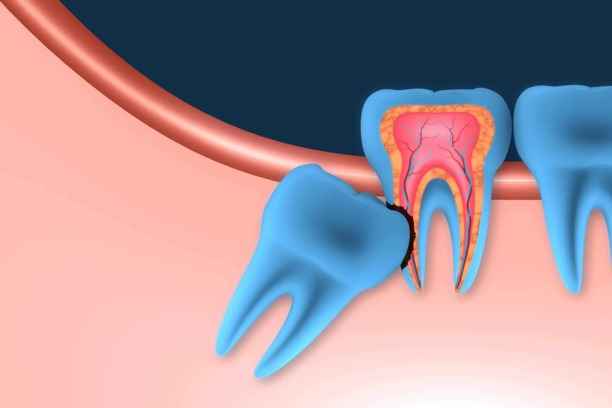

ضرس العقل هو الضرس الثالث والأخير في كل ربع من أرباع الفم، ويُعرف علميًا باسم الضرس الطاحن الثالث. يتميز بموقعه الخلفي العميق، ما يجعله أكثر عرضة للمشكلات مقارنة ببقية الأسنان. غالبًا ما يكون بزوغه غير مكتمل أو منحرفًا بسبب ضيق المساحة، الأمر الذي يؤدي إلى سلسلة من المشكلات المتتابعة. وهنا تبدأ اعراض ضرس العقل في الظهور تدريجيًا، كتنبيه بيولوجي بأن هذا الضرس لا يسلك المسار الطبيعي للنمو. ومع استمرار الضغط والاحتكاك، تتفاقم اعراض ضرس العقل وتتحول من مجرد انزعاج إلى ألم حاد قد يؤثر على جودة الحياة اليومية.

يختلف شكل ضرس العقل من شخص لآخر، إلا أنه غالبًا ما يتميز بحجم أكبر وجذور أكثر تعقيدًا مقارنة ببقية الأضراس. قد يكون مكتمل التكوين أو مشوهًا جزئيًا، وقد يظهر بشكل عمودي أو مائل أو حتى أفقي. هذه الاختلافات الشكلية تلعب دورًا مباشرًا في حدة اعراض ضرس العقل. ومن أبرز السمات الشكلية الشائعة:

• ميلان واضح نحو الضرس المجاور أو باتجاه عظم الفك.

• بزوغ جزئي يترك جزءًا من الضرس مغطى باللثة.

• تموضع عميق داخل العظم دون ظهور مرئي.